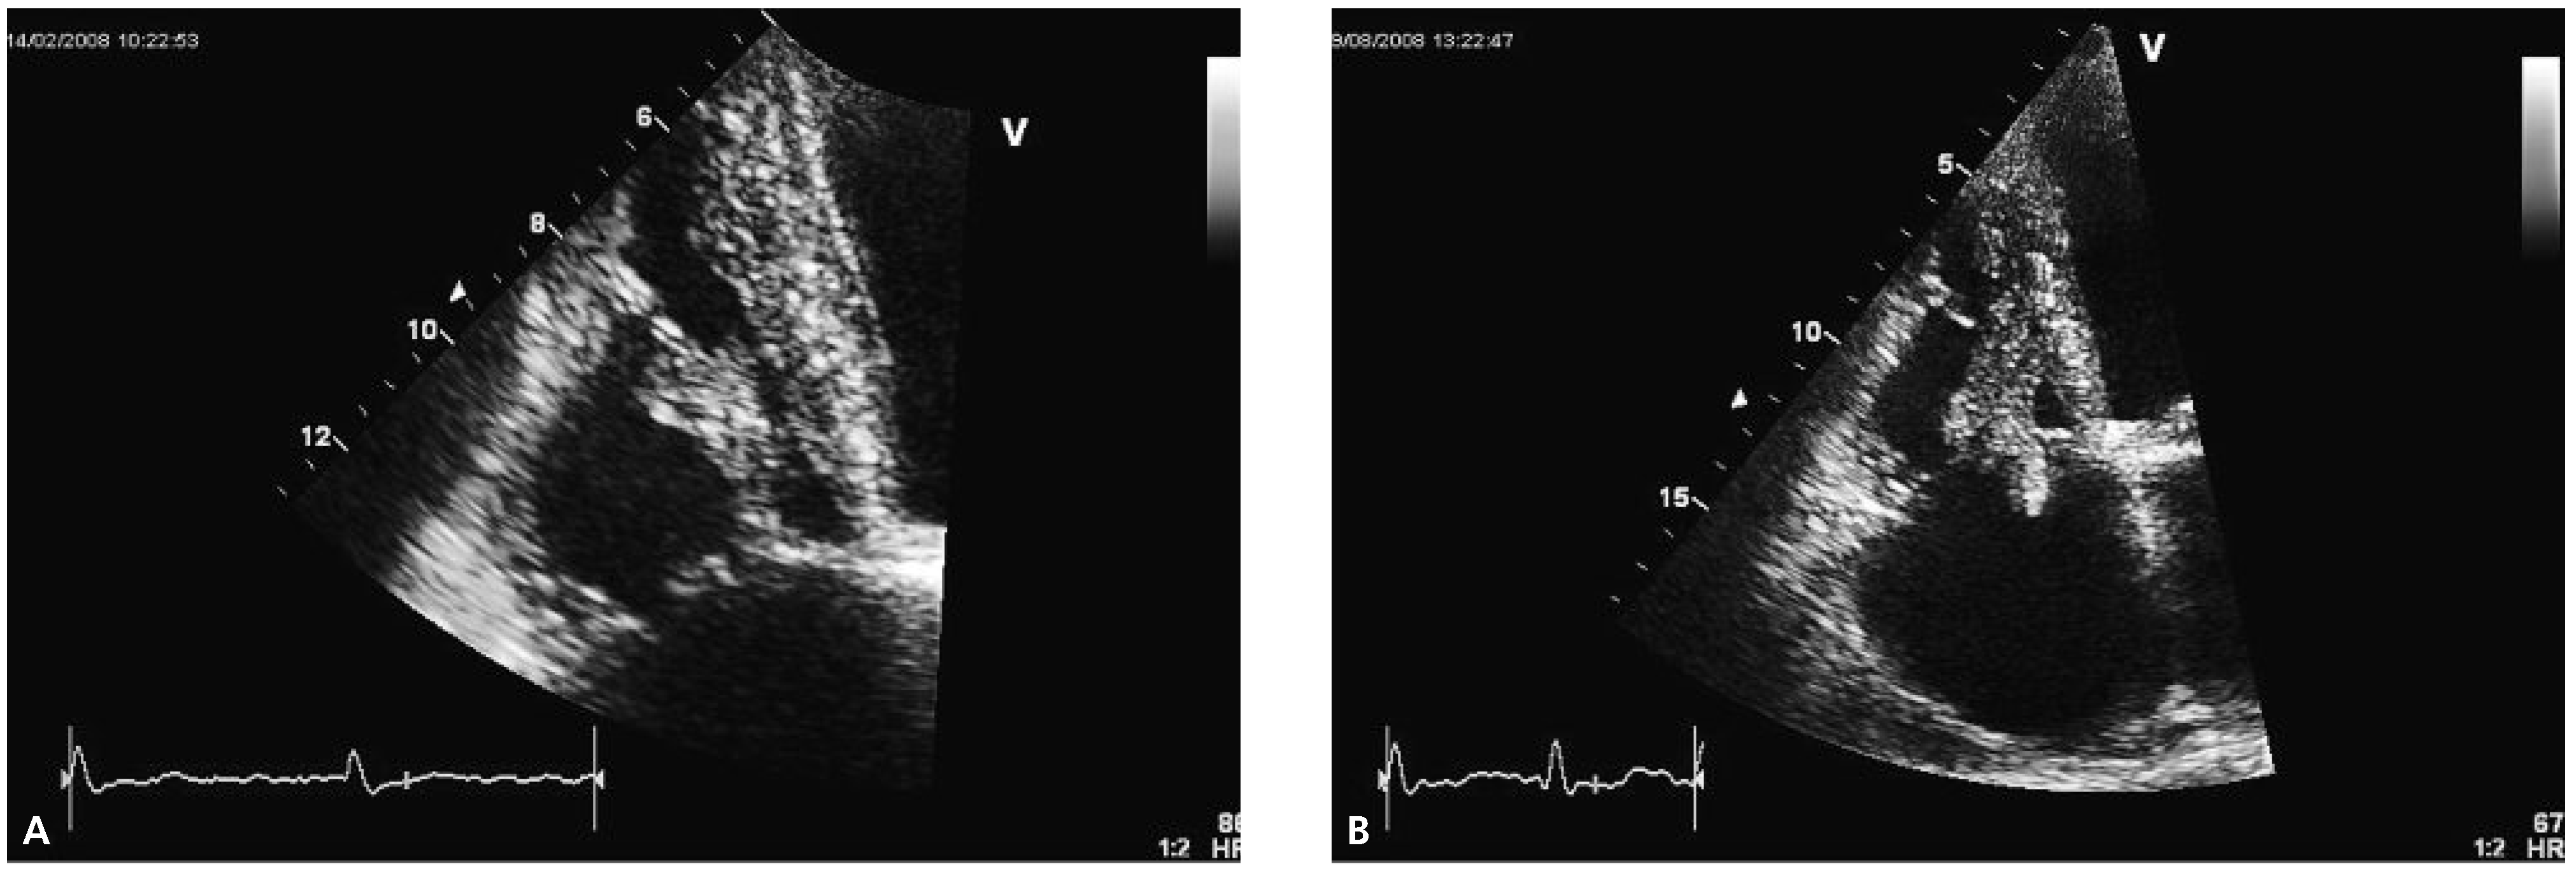

Echocardiography two months later revealed a slightly improved left ventricular ejection fraction (30–35%) and an obvious reduction in size of the thrombus (Figure 2A).

Follow-up echocardiography was performed again half a year later. At that time, the size of the right ventricle appeared normal whereas the systolic right ventricular function was still reduced (TAPSE 1.8 cm, TDI 9 cm/s). The thrombus had increased in size with new highly mobile parts prolapsing into the right atrium (Figure 2B). The patient passed away at home seven months later from an unknown reason.

Figure 2. Echocardiographic follow-up images. Note the increase in size and the prolapsing part of the thrombus in panel (B).